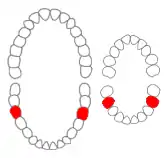

Mandibular first molars of permanent and primary teeth marked in red. | |